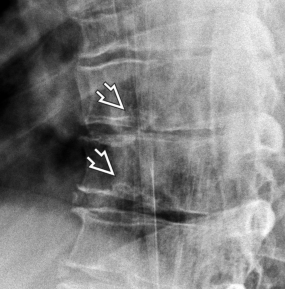

Imagerie

- Vertèbres thoraciques cunéiformes sur 3 niveaux

- Avec >5° de cyphose

- Hernies de Schmorl (intraspongieuses)

- Aspect ondulé (feuilleté) des plateaux

- Perte de hauteur des disques